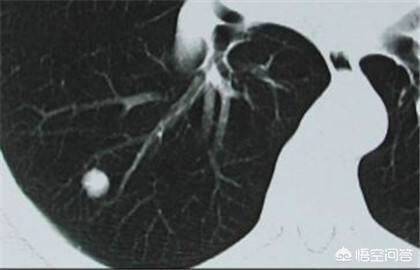

肺结节通俗的讲就是CT上黑色的肺里有小白点。直径大于3cm一般称为肺部肿块,肺癌的可能性相对较大。通常我们将直接小于3cm的圆形或者椭圆形占位病变称之为孤立性肺结节,它被肺实质包围,完全没有相关的淋巴结肿大、肺不张或肺炎。直接小于2cm的称为肺内小结节,直接小于5mm的称为微小结节。

如何判断肺结节是良性还是恶性呢?1.结节的位置:肺癌更多发生于上叶,尤其好发于右肺,但肺结核留下的一些疤痕结节也饿多发于上肺,所以要注意鉴别。2.结节的形态:胸部ct被公认为是鉴别肺部小结节良恶性的最佳检查手段。假如CT上描述有深分叶、短粗毛刺、空泡征、空气支气管征、胸膜凹陷征、肺血管集中征以及明显的强化征等,都认为是恶性征象,千万不可懈怠。如果结节边界光滑,钙化位于病灶中央或为层状、弥漫性和爆米花样则多见于良性病变,结节内有脂肪多见于良性的错构瘤等。3.结节的大小:直径小于5mm,恶性的可能性很小,大约在1%以内;5~10mm时,恶性可能性为6%—28%;直径大于20mm的肺结节恶性概率达到80%。